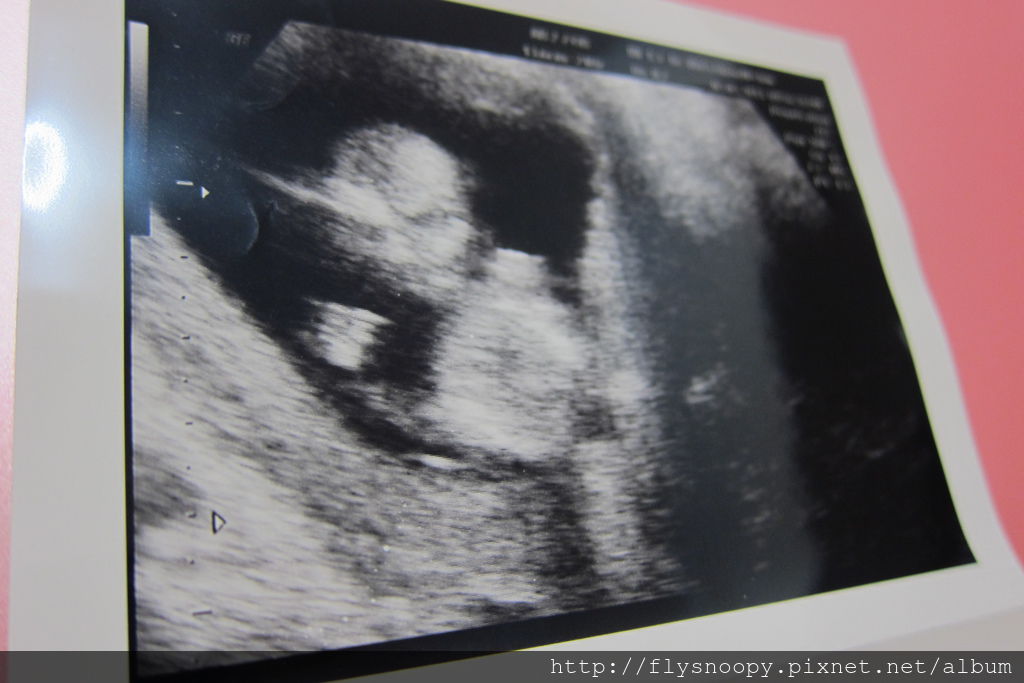

上面三張超音波照片就是這次急診時拍的

這次baby CRL 是7.01,生長一切正常,但是我還是很擔心

醫生說流血就是有流產跡象,所以開藥並要我在家臥床安胎